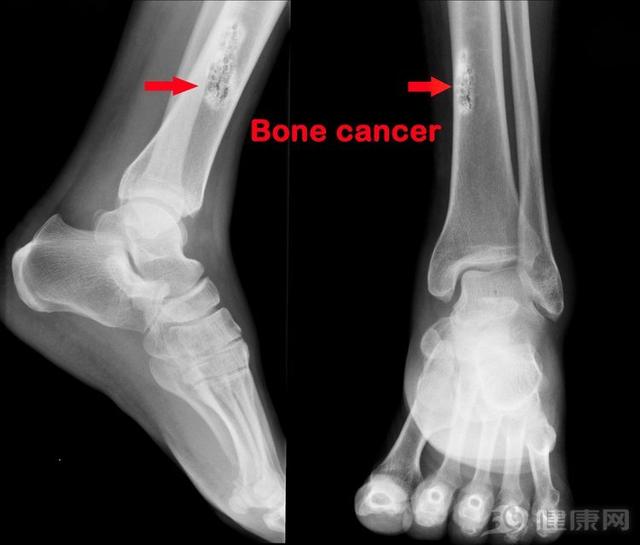

骨癌的初期症状是什么?(腿痛得整夜睡不着)

2019年,医疗纪录片《人间世》第二季上线,第一集《烟花》,将镜头聚焦在上海市第一人民医院骨科骨肉瘤病房的患儿和他们的父母身上。这个病房里的患者都是孩子,最大十几岁,最小7岁,他们都身患一种叫做“骨肉瘤”的疾病。14...